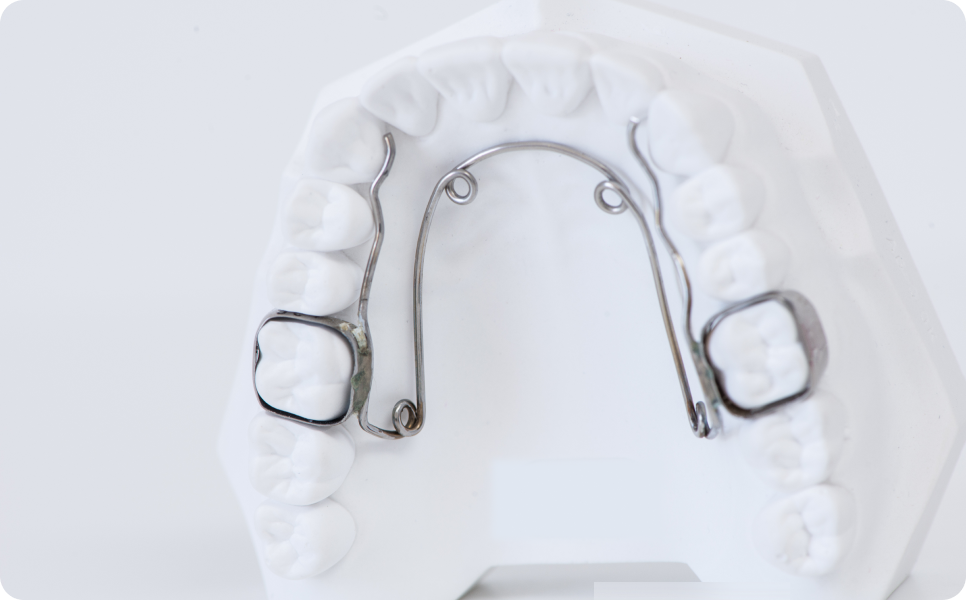

Le Quad Hélix est constitué d’un fil métallique formé de plusieurs boucles (« hélix »), fixé sur les molaires supérieures à l’aide de bagues.